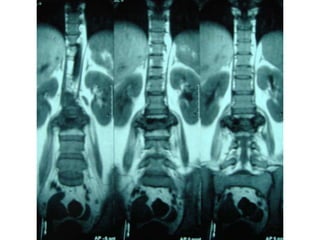

charcot joint

charcot joint by dr khaled abdelbaky